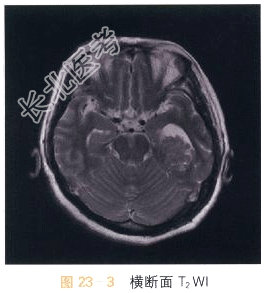

- [材料题] 女,53岁,头痛20天。影像学资料如图23-1~图23-4所示。

读片分析:头颅CT平扫显示左侧侧脑室颞角扩大,内可见不规则形高密度影;MRI检查横断面T₂WI示第三脑室内不规则形异常软组织肿块影,T₂WI等高信号,信号混杂不均,边界尚清晰;DWI呈等信号;增强扫描肿块明显强化,表面呈颗粒状。